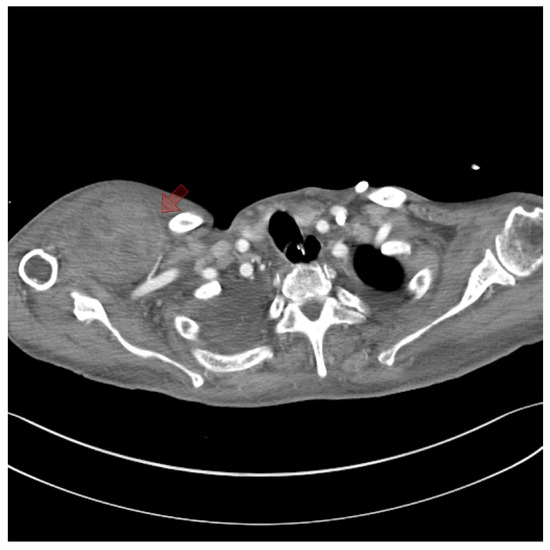

Figure 3. Axial section of the thorax at the axillary level. Computed tomography angiography revealed a branch of the lateral thoracic artery located near the subpectoral hematoma (red arrow).

On the fifth day, surgical exploration revealed a large hematoma beneath the pectoralis major muscle. The hematoma had solidified and showed no signs of infection; culture results were negative. Bleeding was identified from a branch of the lateral thoracic artery within the deep portion of the pectoralis major muscle, as observed on CT angiography (Figure 3). The procedure involved removing the hematoma and ligating the vessel, followed by irrigation, placement of a closed suction drain, and primary closure. The surgery was completed with a mild compressive dressing (Figure 4).